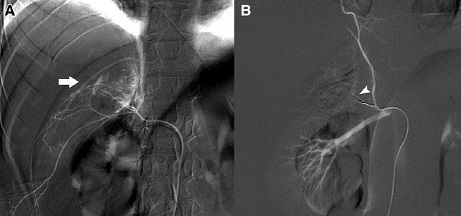

Arteriografía: Así como con la PIV, el advenimiento del TAC ha sustituído en gran medida la realización de arteriografías. La indicación más frecuente es la falta de visualización renal en una PIV cuando no se dispone de TAC y también, en casos excepcionales en lesiones del pedículo vascular cuando no están claros los resultados de la tomografía. En lo últimos años ha recuperado terreno, pero esta vez ligada al tratamiento en los casos donde se decide realizar angioembolización.

Como se mencionó anteriormente, será necesaria la exploración quirúrgica en casos de avulsión o laceración del pedículo renal, inestabilidad hemodinámica a pesar de la reanimación y la presencia de lesiones abdominales asociadas. En casos de sangrado renal activo (hematomas perirrenales) en pacientes estables, podría estar utilizarse la angioembolización selectiva, no existiendo otras indicaciones para cirugía.

La hemorragia es la complicación más importante de la fase aguda, pero pudiera observarse tardíamente, luego de algunos días o semanas desde el traumatismo. Las causas pueden tener relación con la aparición de fístula arterio-venosa o pseudoaneurisma vascular renal. Ambas muy poco frecuentes y de manejo actual mínimamente invasivo con la utilización de embolización percutánea selectiva.

La fístula arterio-venosa y el pseudoaneurisma, son dos complicaciones muy poco frecuentes, asociadas a hemorragia tardía o más frecuentemente asintomáticas, que aparecen varias semanas luego del trauma. Su manejo habitual es la radioembolización.

En casos de sangrado activo, una herramienta que resulta bastante útil es la Angiografía, la cual además posee la ventaja de ser potencialmente terapéutica. Al utilizar esta técnica, el sangrado adrenal activo se aprecia como una extravasación de contraste tras la microcateterización selectiva de sus arterias. Una vez identificado el sangrado se puede embolizar con diferentes materiales como los microcoils, micropartículas o líquidos esclerosantes (23).

Según estos reportes, la angiografía es una adecuada opción de tratamiento para el TGSR y en ocasiones puede hacer innecesaria a la laparotomía. Dado que los pacientes con TGSR tienen frecuentemente lesiones viscerales asociadas, el uso de esta técnica podría utilizarse en el manejo de la hemorragia concomitante.

La embolización angiográfica transcatéter se ha convertido en un método bien establecido para el manejo de la hemorragia adrenal traumática. Existen reportes que establecen la factibilidad y la seguridad de esta técnica para el TGSR en centros de trauma de nivel 1.

En todo caso, si bien la angiografía constituye una buena opción en casos seleccionados, la cirugía es aún obligatoria para el control del sangrado en el TGSR, especialmente cuando los pacientes tienen otras lesiones concomitantes que requieren exploración, o cuando exhiben inestabilidad hemodinámica.